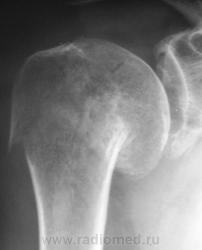

Случай № 1. Пациент направлен хирургом на рентгенографию плечевого сустава. 2 дня тому - травма.

Вколоченный перелом шейки плечевой кости с отрывом большого бугра. Варусная деформация на уровне перелома.